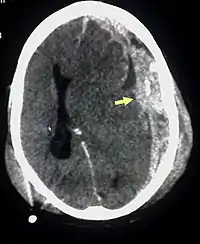

![]() Субдуральна гематома (показана стрілкою), скупчення крові між твердою мозковою оболоною та мозком, що виникла внаслідок струшування дитини. Помітна значна дислокація мозкових структур із зміщенням шлуночків мозку Субдуральна гематома (показана стрілкою), скупчення крові між твердою мозковою оболоною та мозком, що виникла внаслідок струшування дитини. Помітна значна дислокація мозкових структур із зміщенням шлуночків мозку | |

Характерні симптоми ССД — крововиливи в сітківку, субдуральні гематоми[3] (крововилив у мозок) та набряк мозку. Механізм травматичного ушкодження пояснюється трясінням, а також поєднанням тупого удару та трясіння. Можуть спостерігатись поведінкові розлади, труднощі з годуванням, зневоднення, дратівливість, судоми, зміна свідомості до коматозного стану. Лікар також може виявити розлади дихання від респіраторного дистрес-синдрому до апное, тахікардію. ССД іноді супроводжуеться зупинкою дихання.